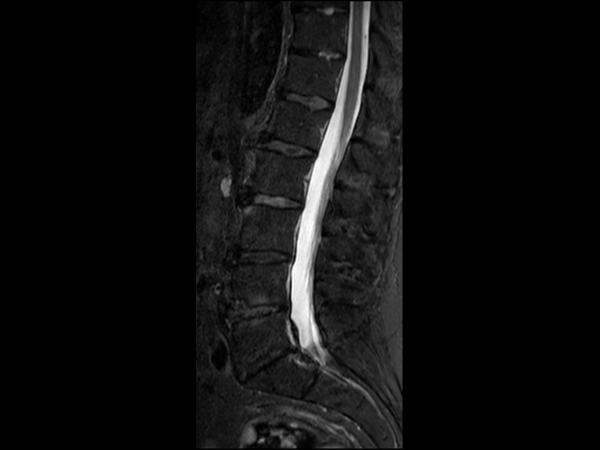

Comprehensive Lumbar Spine imaging at 3.0T